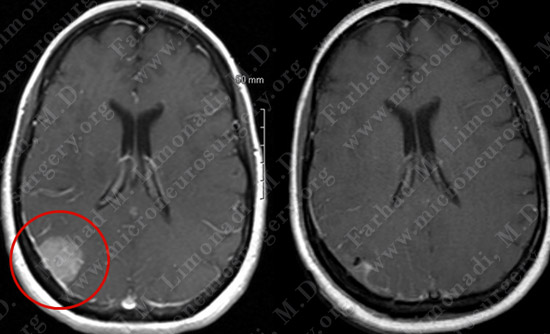

Post-op Imaging

Before Operation                                                 After Operation

Post-op MRI shows complete resection of the tumor with no injury to surrounding neurovascular structures.